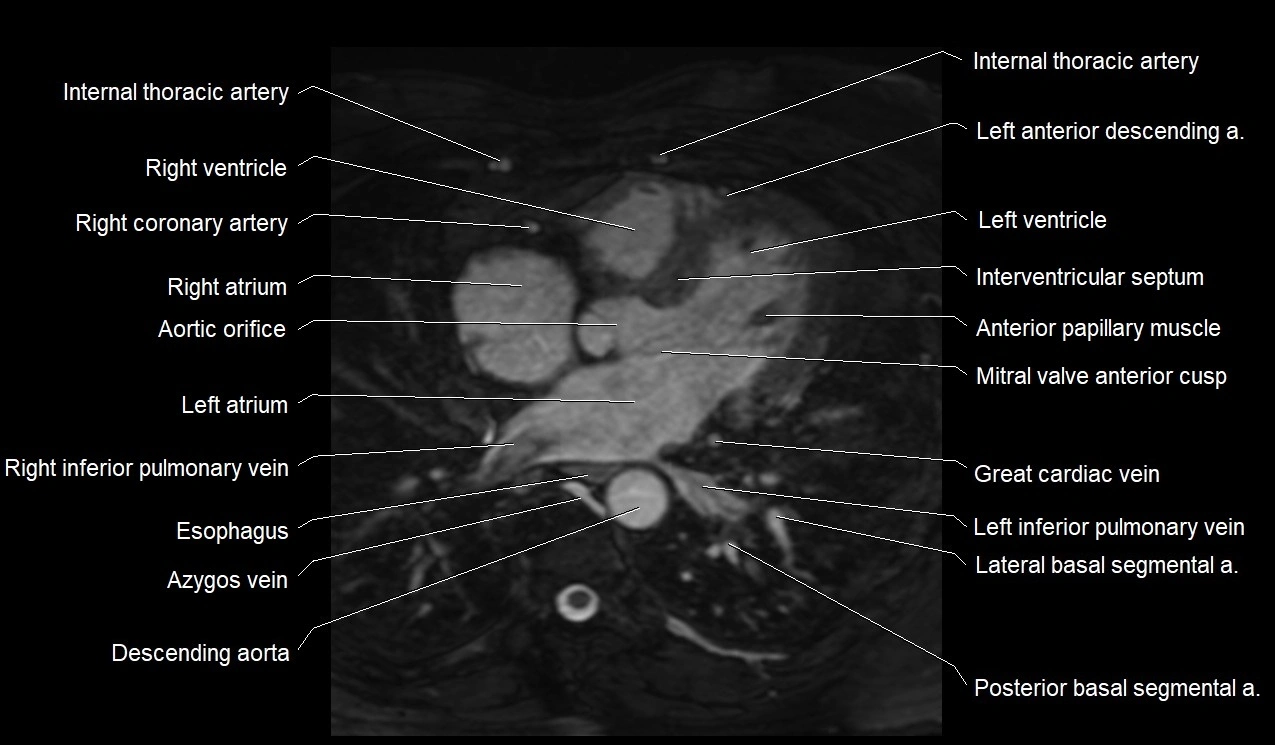

MRI image